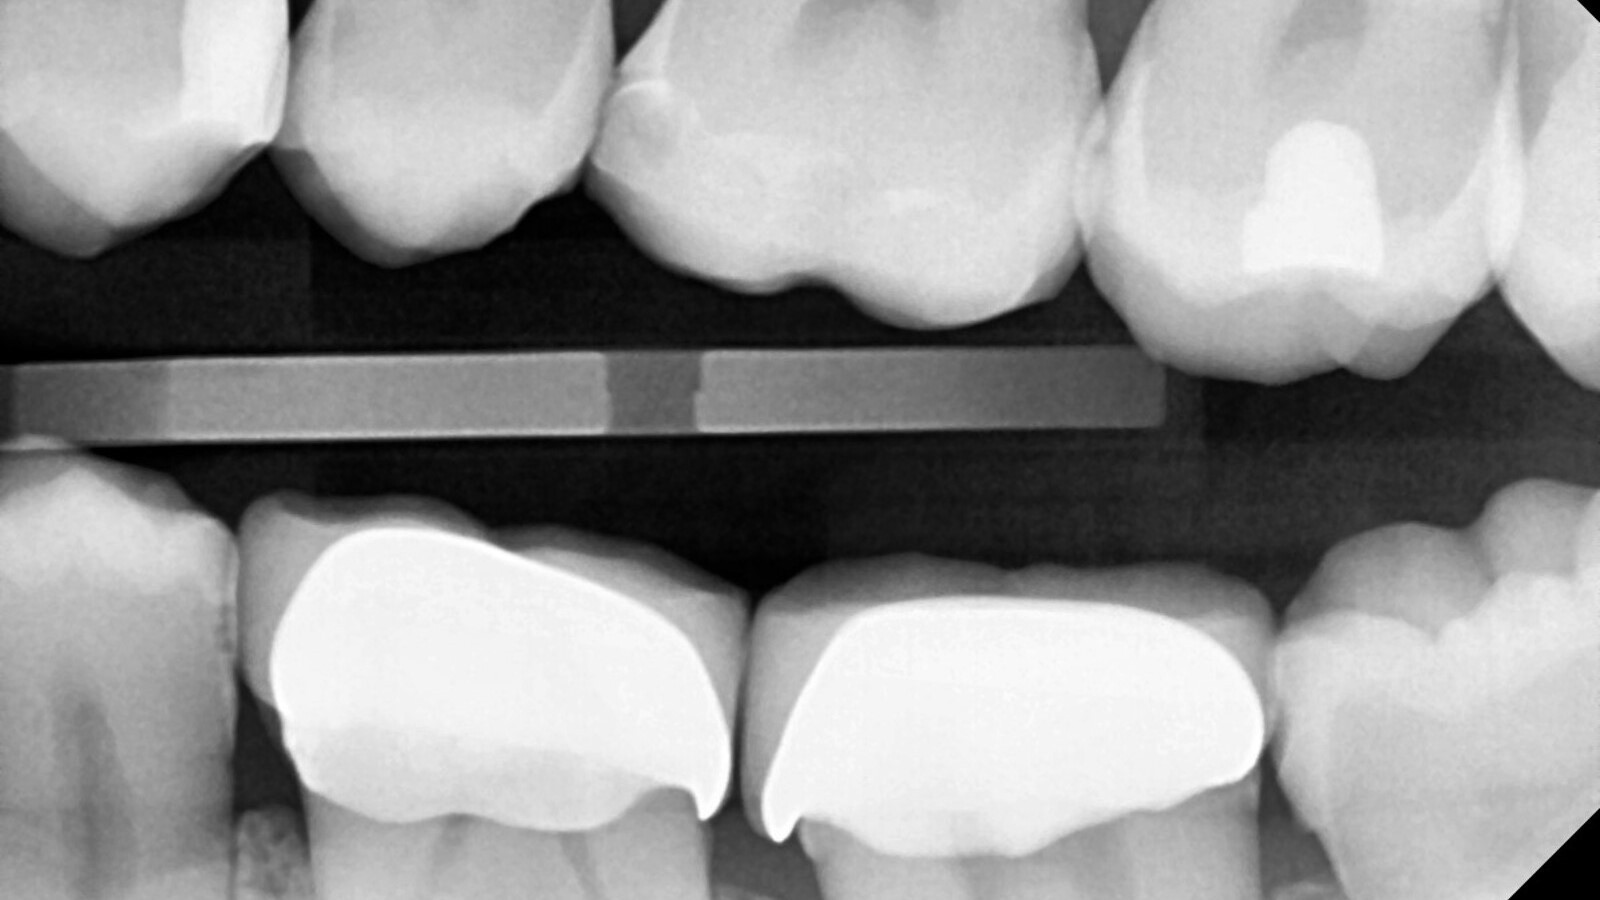

Le professeur Ernst a d'abord identifié les caries non visibles et a ouvert la lésion carieuse pour montrer le problème au patient (Fig. 1-2). Il a ensuite excavé la carie, préparé la cavité et placé une matrice sectionnelle (Fig. 3) avant de sceller la cavité avec de l'adhésif (Fig. 4). En une seule étape, il a rempli la cavité avec Venus Bulk Flow ONE (Fig. 5). Une fois la restauration terminée, le Pr Ernst l'a polie (Fig. 6) et a pris une radiographie de contrôle, qui montre également l'excellente radiopacité de Venus Bulk Flow ONE (Fig. 7).